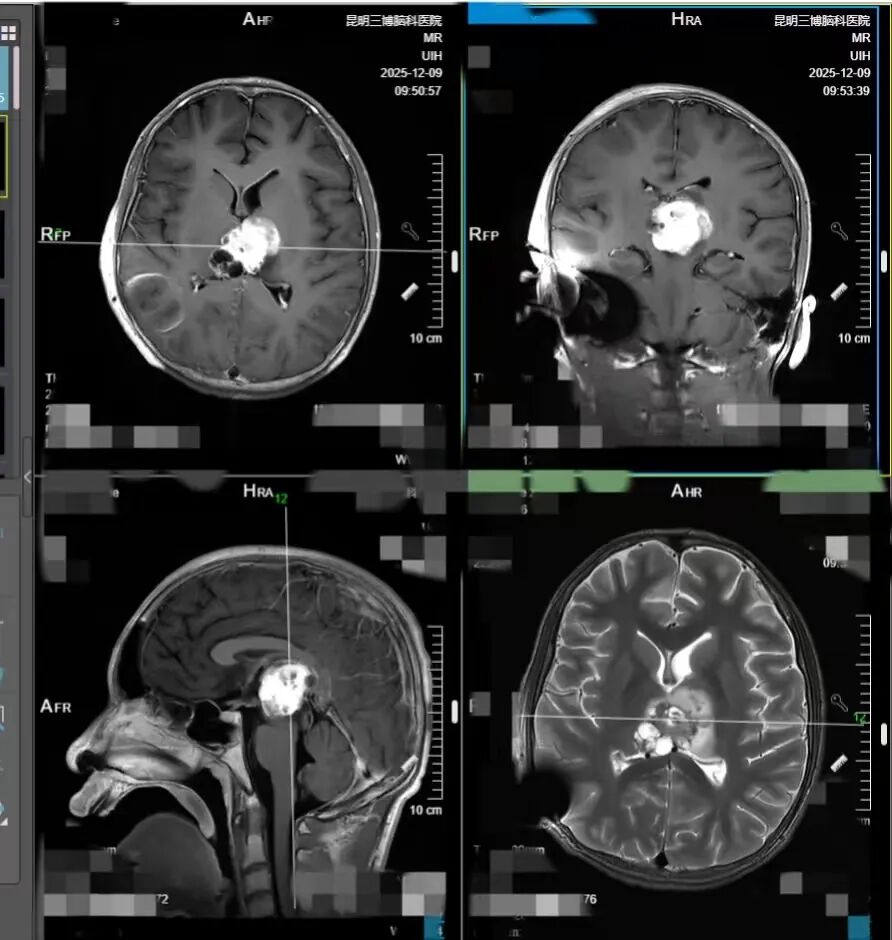

时间就是生命。张宏伟教授立即牵头,组织昆明三博脑科医院相关科室骨干与首都医科大学三博脑科医院化疗专家开展多学科会诊,反复研讨后敲定了精准的化疗方案。12 月 1 日下午,小熙就顺利接受了第一次化疗。

化疗过程如同在刀尖上行走,医生团队全程严密监测小熙的生命体征,根据小熙的身体反应精细调整药物剂量,每一个决策都慎之又慎。幸运的是,化疗之路比预想中平稳。随着肿瘤开始逐渐缩小,脑积水得到缓解,颅内压也慢慢恢复正常,小熙的意识开始苏醒——从毫无反应的昏迷,到能睁开眼睛的嗜睡,再到后来可以清晰应答、自主进食,甚至能下床活动。